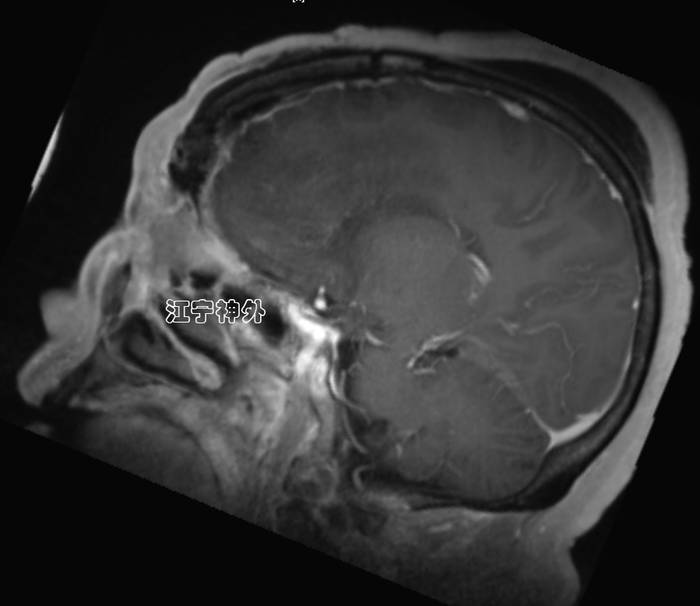

郑学胜团队予以术前磁共振检查发现,前颅窝底巨大脑肿瘤,伴有大片脑水肿,双侧侧脑室和第三脑室明显受压变小,下丘脑、左侧基底节等神经结构亦受明显推挤。肿瘤血供丰富,与双侧大脑前动脉关系复杂。